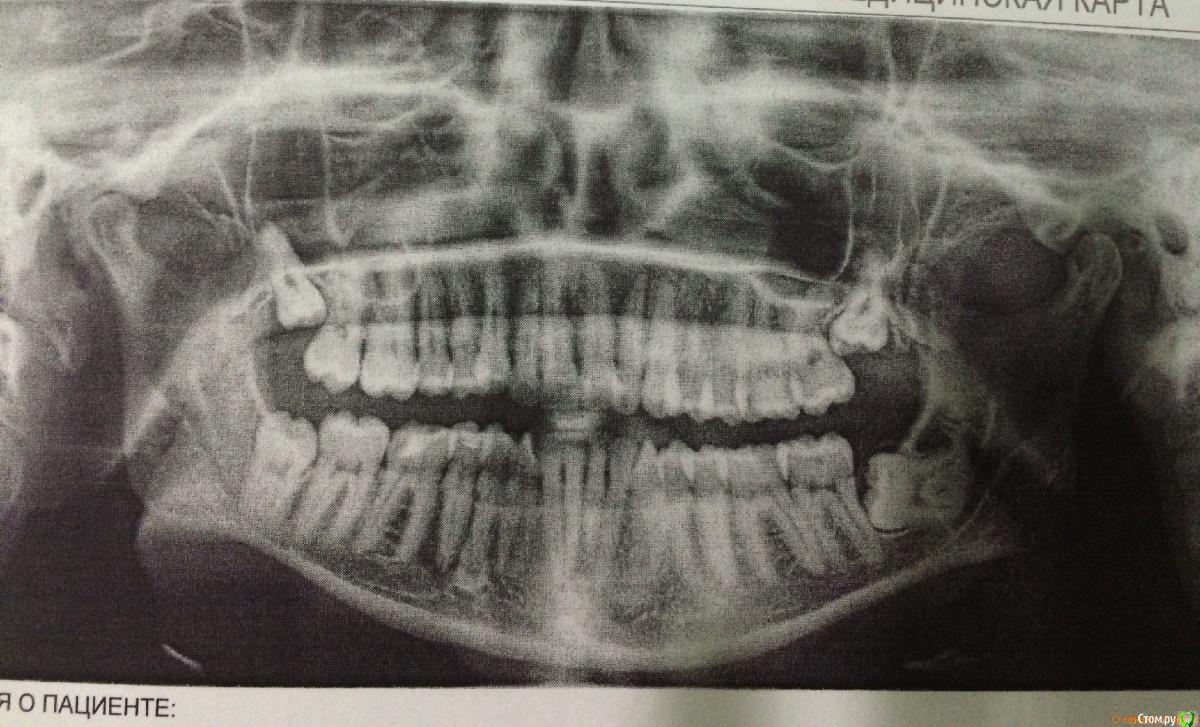

shante Опубликовано 12 сентября, 2015 Поделиться Опубликовано 12 сентября, 2015 7.09 удалили две 8-к справа. Хирург сказал что нижняя лежит близко к нерву, верхнюю удалили легко и быстро нижнюю пилили. Наложили швы, в лунку положили рассасывающуюся губку. Был курс антибиотиков 5 дней и ванночки хлоргексидином. После операции отек сошел быстро, сильные боли были только в 1 день, есть только онемение подбородка. Сегодня ходила на осмотр - сказали заживает все хорошо и швы почти рассосались, онемение пройдет через пару месяцев. Но я сегодня не пила обезболивающе, т.к. утром чувствовала себя хорошо, и к вечером были сильные боли на пол рта. Болели десна в местах удаления 8 рок и 6-ки, боль то была в деснах то переходила в зубы или болела вся правая половина. Так плохо было только в день операции. Прошло только после таблетки нурофена и пакетика нимисила. В понедельник еду в другую клинику на компьютерную томографию другой 8-ки которая лежи горизонтально и более сложная т.к. дальше удалять планирую с седацие. Нормально ли что есть такие сильные боли после удаления через 5 дней? Если нет какие снимки мне еще сделать в понедельник чтобы найти причину боли?До удаления ходила к терапевту, проблем с зубами не обнаружено, была проф чистра. Ссылка на комментарий

shante Опубликовано 18 сентября, 2015 Автор Поделиться Опубликовано 18 сентября, 2015 Сделала КТ, сказали еще неделя должна пройти если будет болеть то есть воспалительный процесс. По второму зубу - хирург планирует оставить корни т.к. они лежат слишком близко к нерву. Как живут пациенты с корнями? Врач сказал что очень редко они выходят а так остаются неподвижными. Ссылка на комментарий

shante Опубликовано 30 сентября, 2015 Автор Поделиться Опубликовано 30 сентября, 2015 Отменила все из-за командировки - коллеги и родственники отговорили удалять за неделю до отъезда. Показывала КТ еще 2 хирургам:1 - корни надо удалять, верхний задевает гайморову пазуху и там есть киста (удалять можно только в стационаре т.к. те хирурги могут "лезть" в гайморову пазуху если кусочек корня по время удаления попадет туда). я так поняла этот врач такими зубами не занимается. 2 - хирург из стационара советует удалять с корнями, верхний зуб ничего сложного, нижний сложное удаление. сказал губа и подбородок онемеют и чувствительность вернется через несколько месяцев только. Ссылка на комментарий